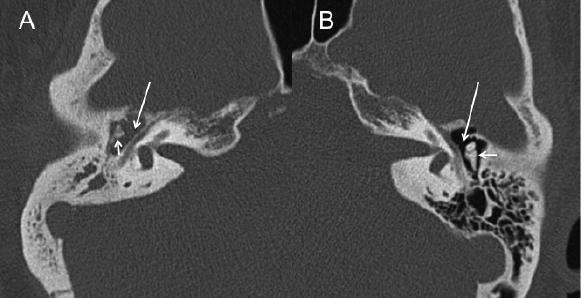

• What type of imaging is shown in the image?

Computed tomography (CT)

• The image shows axial slices of the temporal bone.